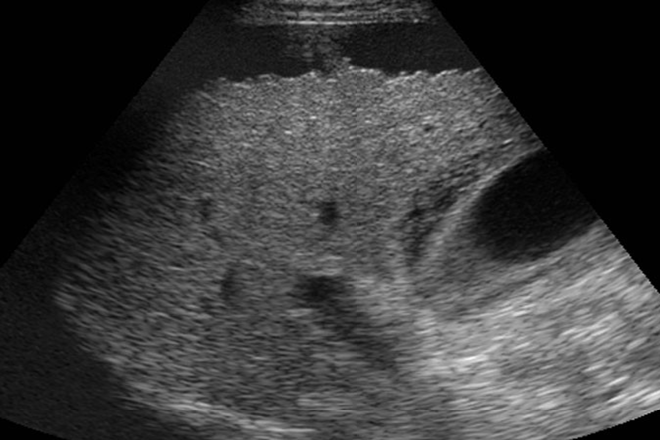

Hallazgos ecográficos con contraste en paragonimiasis hepática.

Se ingresan al hospital 15 pacientes con paragonimiosis la ultrasonografia convencional se realizó con Philips con un 15-MHz transductor convexo. Se administró la inyección en bolo de 2,4 ml de un agente de contraste hexafluoruro de azufre-micro burbuja. Se revisaron retrospectivamente y correlacionados con los hallazgos patológicos. Todos los pacientes fueron sometidos a cirugia y el diagnóstico confirmado histologicamente. Los principales hallazgos patológicos incluyen: necrosis coagulativa o licuefacción dentro de la lesión, Infiltración de un gran número de eosinófilos con la formación de abscesos eosinofílica crónica y esporádica distribución de los cristales de Charcot-Leyden, y hiperplasia de tejido granulomatoso y fibroso alrededor de la lesión.

Comentario. De acuerdo al estudio realizado se puede encontrar su propia imagen utrasonografica que nos haga sospechar en paragonimiasis, con una imagen hipoecoica subcapsular, aun siendo la paragonimiasis poco común habría que sospecharla.